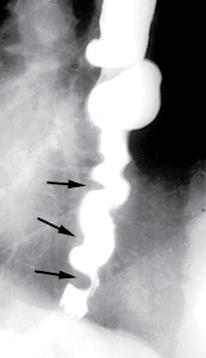

A motilidade esofágica é considerada anormal se os achados de motilidade excederem dois desvios padrão daqueles encontrados em um grande grupo de indivíduos normais. Embora as implicações clínicas de alguns distúrbios da motilidade esofágica, como a acalásia, sejam claras, há considerável controvérsia em relação às implicações clínicas de outras anormalidades da motilidade esofágica encontradas nos testes de manometria esofágica e se eles causam ou explicam os sintomas do paciente.

Disponível em: https://www.uptodate.com/contents/image?imageKey=GAST%2F69821&topicKey=GAST%2F2256&search=motilidade%20esof%C3%A1gica&rank=1~91&source=see_link

A imagem representa qual distúrbio de motilidade esofágica?